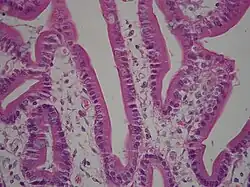

A brush border (striated border or brush border membrane) is the microvillus-covered surface of simple cuboidal and simple columnar epithelium found in different parts of the body. Microvilli are approximately 100 nanometers in diameter and their length varies from approximately 100 to 2,000 nanometers. Because individual microvilli are so small and are tightly packed in the brush border, individual microvilli can only be resolved using electron microscopes;[1] with a light microscope they can usually only be seen collectively as a fuzzy fringe at the surface of the epithelium. This fuzzy appearance gave rise to the term brush border, as early anatomists noted that this structure appeared very much like the bristles of a paintbrush.

- The small intestine tract: This is where absorption takes place.[2][3][4] The brush borders of the intestinal lining are the site of terminal carbohydrate digestions. The microvilli that constitute the brush border have enzymes for this final part of digestion anchored into their apical plasma membrane as integral membrane proteins. These enzymes are found near to the transporters that will then allow absorption of the digested nutrients.

In intestinal cells, the microvilli are referred to as brush border and are protoplasmic extensions contrary to villi which are submucosal folds, while in the kidneys, microvilli are referred to as striated border.[8]